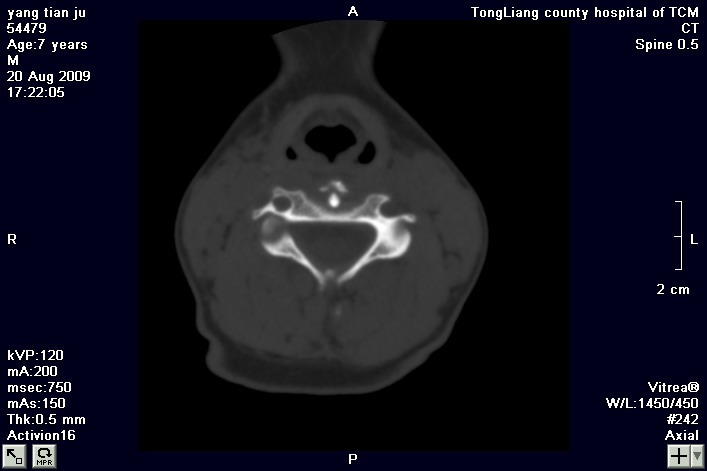

标题: PED2853:颈3/4椎间盘内高密度钙化灶,请各位会诊. [打印本页]

标题: PED2853:颈3/4椎间盘内高密度钙化灶,请各位会诊.

患儿,7岁,颈部疼痛3天,颈部活动受限.

本例应该是典型的儿童钙化性椎间盘病。

儿童钙化性椎间盘病发病年龄多在5~12岁,男女比例相当,大多数患儿发病主要表现为颈部疼痛,伴活动受限。少数有吞咽不适或肢体瘫痪。有一部分患儿无症状,是在其它检查时发现。病因尚不完全明了,可能的有:1、感染。2外伤。

儿童颈椎椎间盘钙化系一良性自限性疾病,可见于颈、胸、腰椎,以颈椎为多发,腰椎少见,多为单发。钙化位于髓核,也可累及软骨板和纤维环引起钙化主要发生于c 4~7  的髓核位于椎间隙正中或偏后,少数向前疝出,以后部多见,呈梭状、盘状、团块状或半环状;(2)颈椎生理曲度变直,椎间隙正常或增宽;(3)相邻椎体可变扁,局部凹陷变形,椎体前下缘鸟嘴状增生,或呈钳口状改变,椎前软组织增厚及环枢椎半脱位;(4)ct可清晰显示椎间盘髓核 位置的钙化灶及经破裂的纤维环向椎管内突出。(5)mri,钙化在t1及t2加权像上均呈低信号,并可见脊髓组织内异常信号。